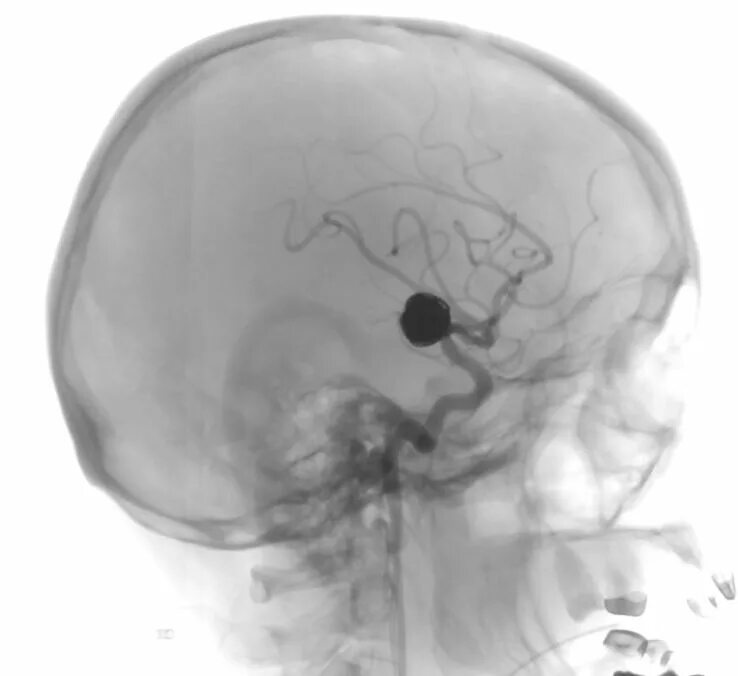

Мешотчатая аневризма внутренней